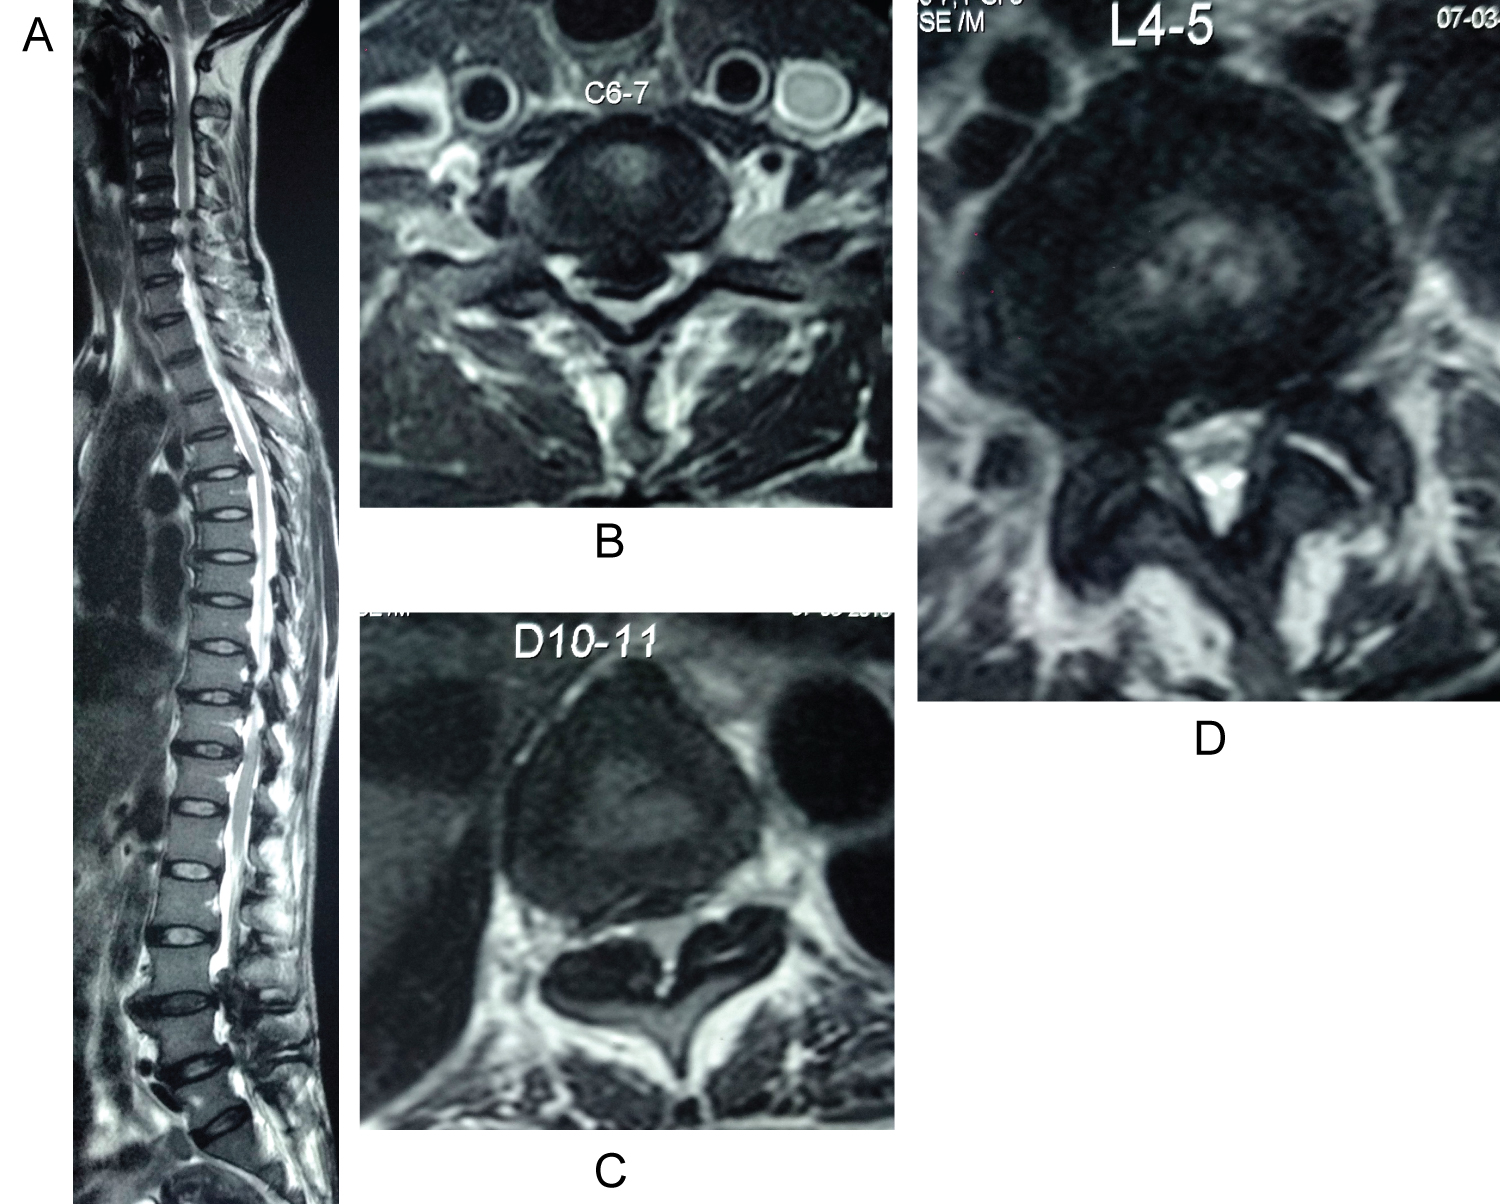

An 80-year-old farmer was referred with bilateral leg pain with inability to walk for long distances since 1 year. He also had started developing weakness of both lower limbs since 6 months. Weakness had progressively worsened and now patient was losing balance while walking. Patient didn't have any complaints related to bowel or bladder dysfunction. Hoffman reflex and Grip sign was positive with hyperreflexia in both upper limbs. Both Knee and ankle reflexes were hyporeflexic. Power in all joints of upper and lower limbs was grade 4. Spasticity was uniform in all 4 limbs. Babinski's sign was absent bilaterally. In view of contrasting clinical picture, MRI cervical and lumbar spine with whole spine screening was done. MRI revealed Triple-Region Spinal Stenosis. It showed Cervical canal stenosis from C5 to C7 with myelomalacia signals in cord. At thoracic spine, stenosis was seen at D10-11 level due to Hypertrophied ligamentum flavum. Opinion of three different radiologists was taken who confirmed absence of cord oedema or myelomalacia at that level. On MRI Lumbar spine, significant canal stenosis was observed at L3-4 & L4-5. Patient was a known case of IHD and was treated with CABG 6 years back.

Management: Since spasticity was same in both upper and lower limbs, C5-6, C6-7 ACDF was carried out in stage one and L3-L5 Microscopic posterior decompression was carried out in stage two, 4 days later. Staged procedure was carried out keeping the co-morbidities of the patient in mind. Following the procedure, Patients' gait imbalance improved to a great extent by 8 months with Nuric grading improving to Grade 1 from Grade 3, with no bladder/bowel complaints. As a result, thoracic decompression was not carried out and the patient has been on a close watch for 1.5 years post op (Figure 1).

Figure 1: Whole spine sagittal cut showing TRSS at C5-C7, D10-11, L3-5. Axial section at the level with maximum compression - Cervical cord at C6-7, Thoracic cord at D10-11 and Lumbar spine at L4-5. View Figure 1